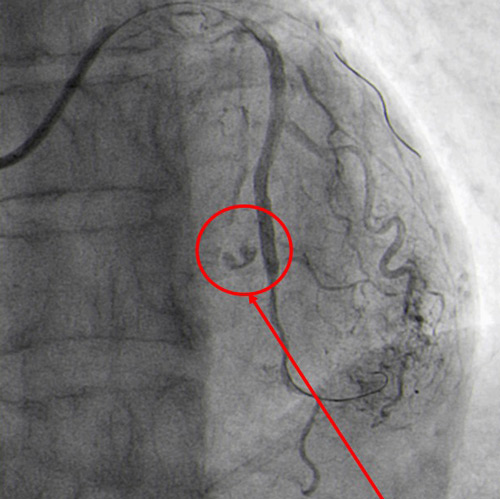

After overlapping post-dilatation, Type III coronary perforation and sudden cardiac tamponade occurred (Figure 6.2).

Type III perforation and cardiac tamponade (Figure 6.2)